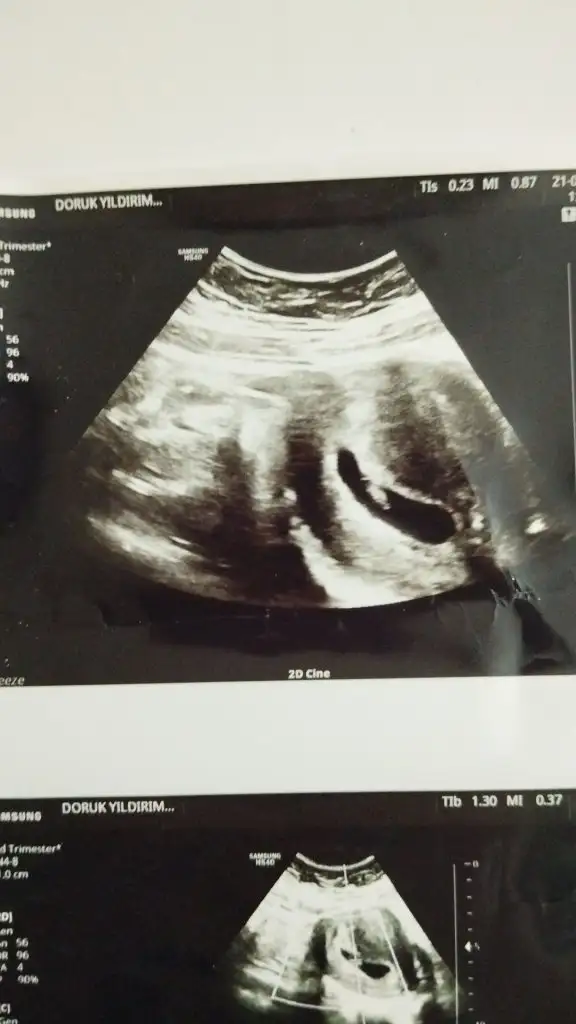

Bende çok merak ettim bak şimdi 3 gebeliğin bu 2 ohlum var bakalım bu ne olacak hayırlısıyla 10 haftalik fotoğrafı karından ultrason